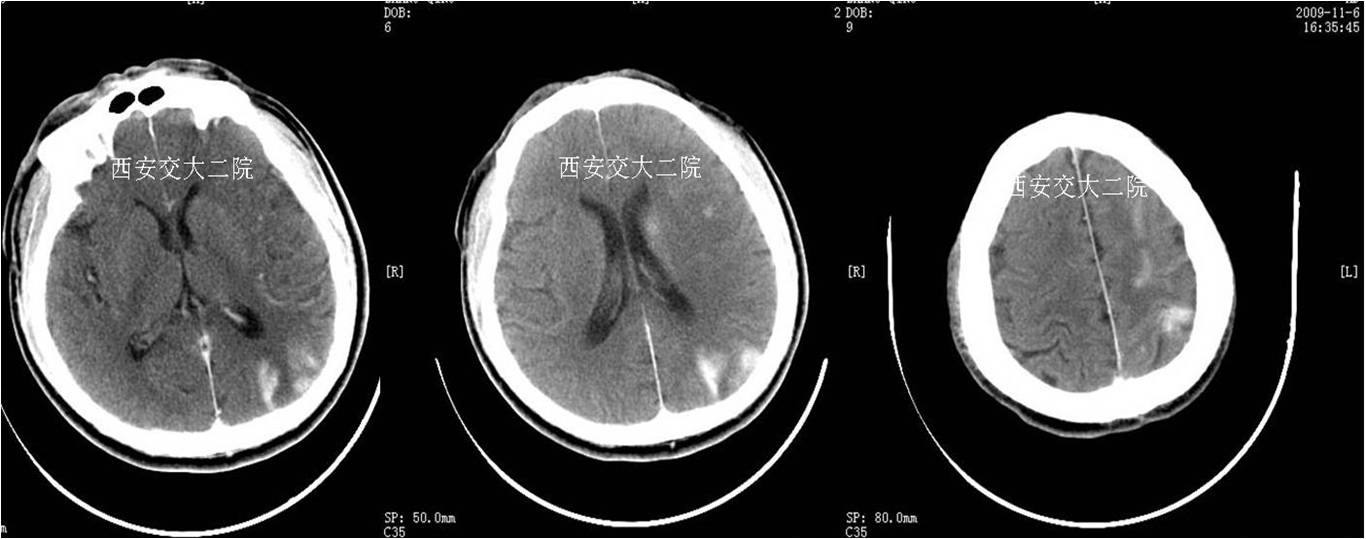

术前CT(病后1h)

术后24小时脑CT

急诊脑CT

术后即刻CT

术后5天脑CT